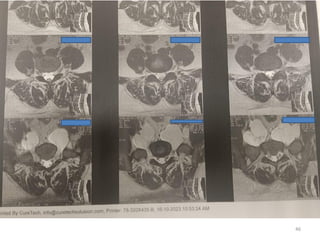

Radiologic assessment

Magnetic Resonance Neurography (MRN)

relation to surrounding structures

Extent of involvement